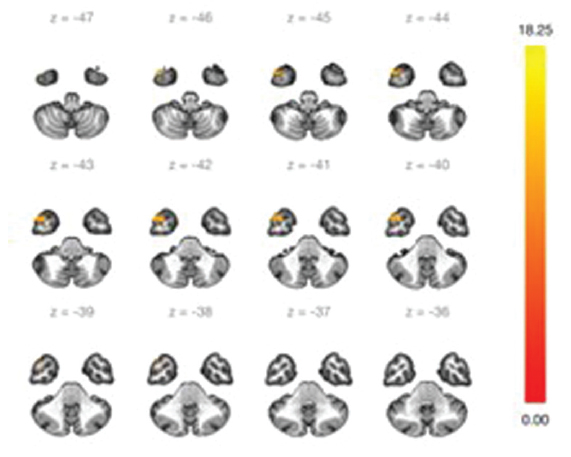

Изменения были обнаружены в следующих нейросетях: СПРРМ, сенсомоторная нейросеть, сеть дорзального внимания, фронтопариетальная сеть, передняя и задняя мозжечковые нейросети (табл. 2).

Оценка сенсомоторной нейросети (СМС)

СМС — это нейросеть покоя, которая является основной при выполнении каких-либо двигательных действий (табл. 3).

Таблица 3. Кластеры сенсомоторной нейросети

Table 3. Clusters of the sensorimotor neural network

№ кластера | Расположение (x, y, z) | Размер кластера | FWR | FDR | p-unc | peak p-FWE | peak p-unc | Локализация кластера |

1 | +06, +58, +22 | 371 | 0,000000 | 0,000000 | 0,000000 | 0,006336 | 0,000000 | Правая лобная доля, левая лобная доля, верхняя лобная извилина слева, верхняя лобная извилина справа, парацингулярная извилина слева, парацингулярная извилина справа |

2 | +36, +46, +14 | 190 | 0,000100 | 0,000069 | 0,000002 | 0,974484 | 0,000027 | Правая лобная доля, средняя лобная извилина справа |

3 | –50, +08, –42 | 141 | 0,001061 | 0,000382 | 0,000022 | 0,840376 | 0,000011 | Левая височная доля |

4 | +48, –46, +12 | 140 | 0,001117 | 0,000382 | 0,000023 | 0,776472 | 0,000008 | Угловая извилина справа, средняя височная извилина, височно-затылочная область справа, задний отдел супрамаргинальной извилины справа |

Примечание. FWR — Family-Wise Error Rate, значение p при групповой вероятности ошибки; FDR — False Discovery Rate, значение p при частоте ложных обнаружений; p-unc — нескорректированное значение p; peak p-FWE — пиковое значение p при групповой вероятности ошибки; peak p-unc — пиковое нескорректированное значение р | ||||||||

При оценке 1-го и 2-го кластеров сенсомоторной нейросети отмечается увеличение функциональной коннективности в области лобных долей (рис. 4, 5).